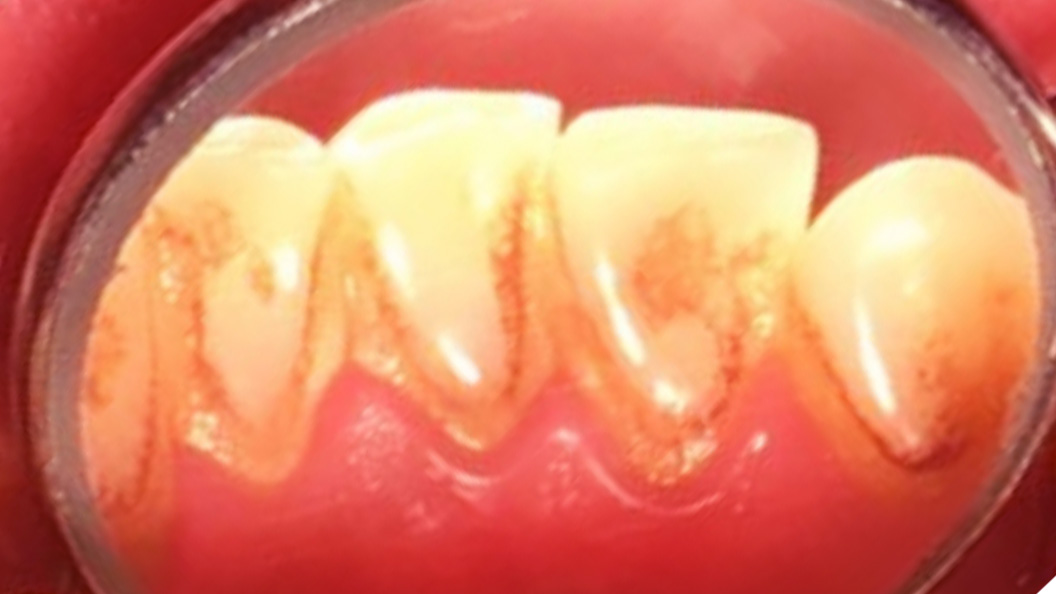

До и после лечения

У пациентки «Стоматологии Комфорта» были жалобы на кровоточивость дёсен во время чистки зубов. Также во время осмотра был обнаружен налёт на поверхности зубов. В результате поставлен диагноз: хронический генерализованный катаральный гингивит.

В процессе лечения были проведены мероприятия:

- проведена профессиональная гигиена полости рта;

- завершающая чистка зубов пастой Detatrine.